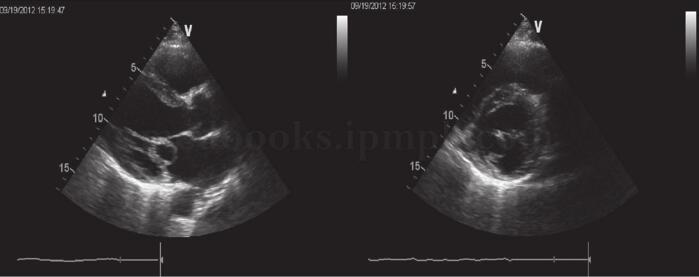

LA 3.7cm、LV 4.8cm、EF 60%;左房轻度增大,收缩期二尖瓣前后叶突向左心房,并超过瓣环水平,可见二尖瓣呈明显气球样改变,瓣叶变厚,冗长。收缩期左房侧可见少量反流信号(图26-1)。

图26-1 二尖瓣脱垂的二维超声心动图

思维提示:重要的检查结果为超声心动图表现为收缩期二尖瓣前后叶突向左心房,并超过瓣环水平。结合患者的病史和体格检查结果,进一步支持二尖瓣脱垂的诊断。